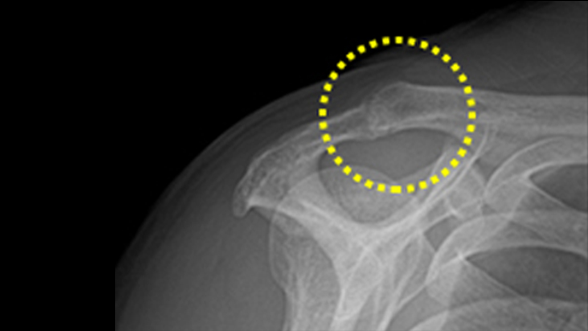

회전근개 파열

어깨뼈를 덮고 있는 네 개의 힘줄(극상근, 극하근, 견갑하근, 소안근)인 회전근은 어깨관절의 안정성을 유지하며

팔을 회전시키는 역할을 합니다. 회전근개의 파열은 회전근이 다양한 원인으로 인해 파열된 상태를 말합니다.

비수술 치료 : 약물, 고정치료 (깁스 또는 보조기), 물리치료, 주사치료, 도수치료

수술치료 : 회전근개 봉합술, 인공관절 치환술